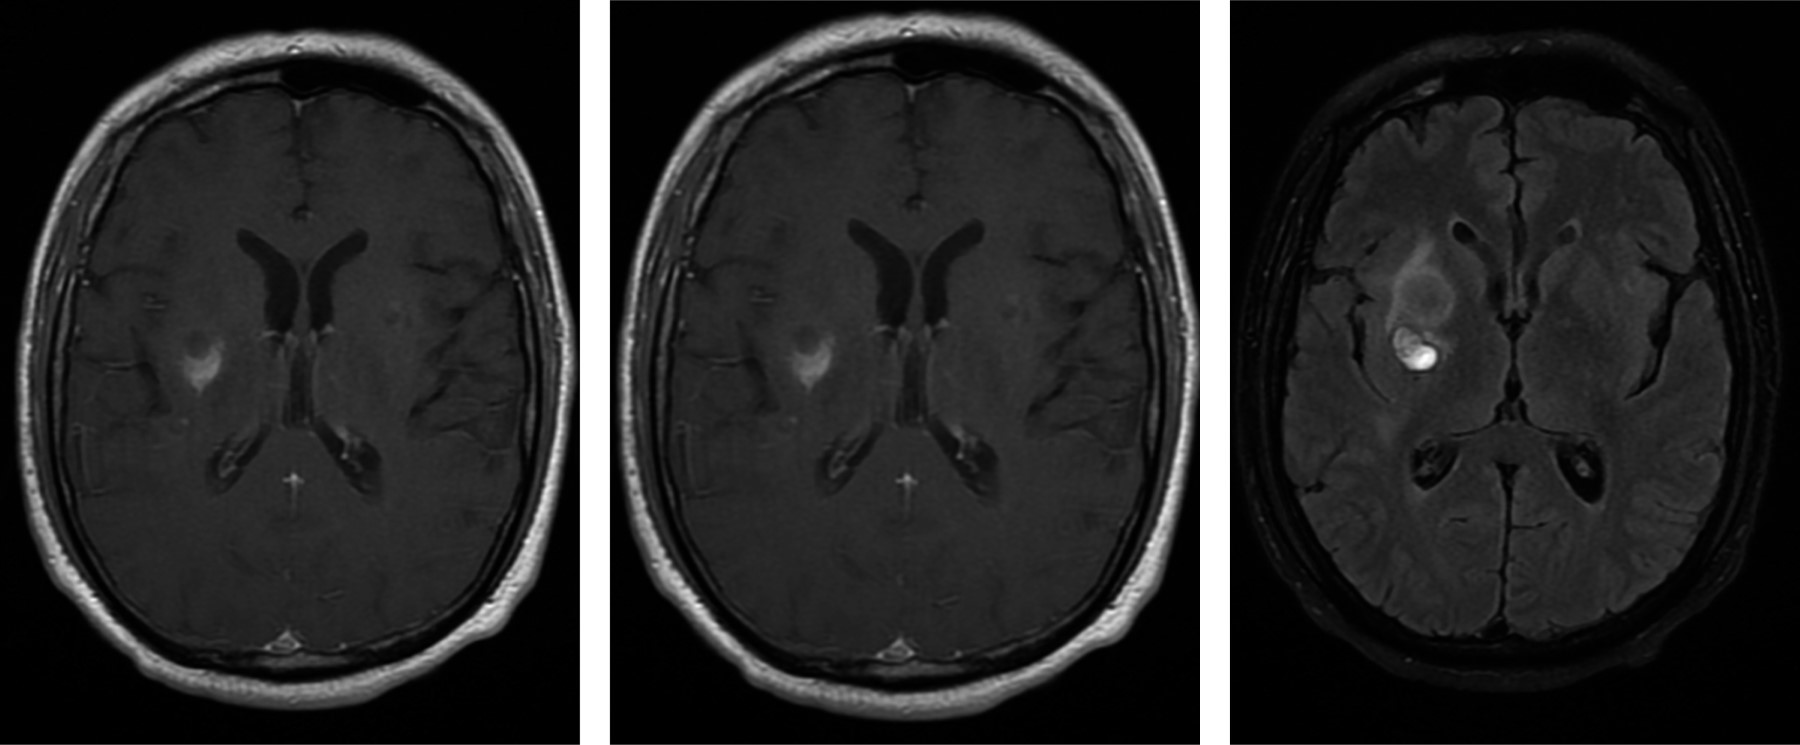

Sin embargo, paciente reconsulta al mes del egreso por presentar nuevamente cefalea de las mismas características, para lo cual se toman nuevas neuroimágenes (Figura 3).

Figura 3